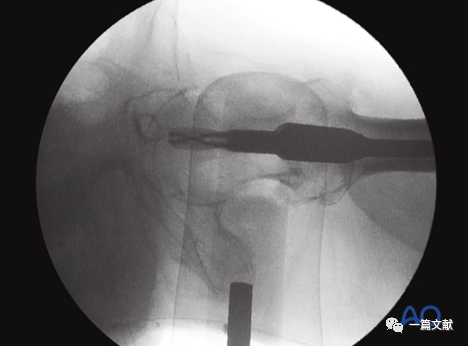

轴位片的作用:判断复位质量;观察头颈骨块与股骨干对线情况;确定导针准确的置入点。如下图:

轴位片上标准的内固定位置(中心到中心)